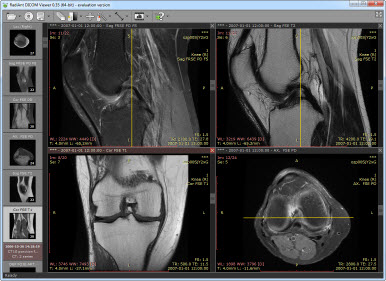

DICOM(Digital Imaging and Communications in Medicine)은 표준 의료영상/기록 포맷이다:

Figure 1.23 DICOM 뷰어를 통한 의료 영상 데이터 관리